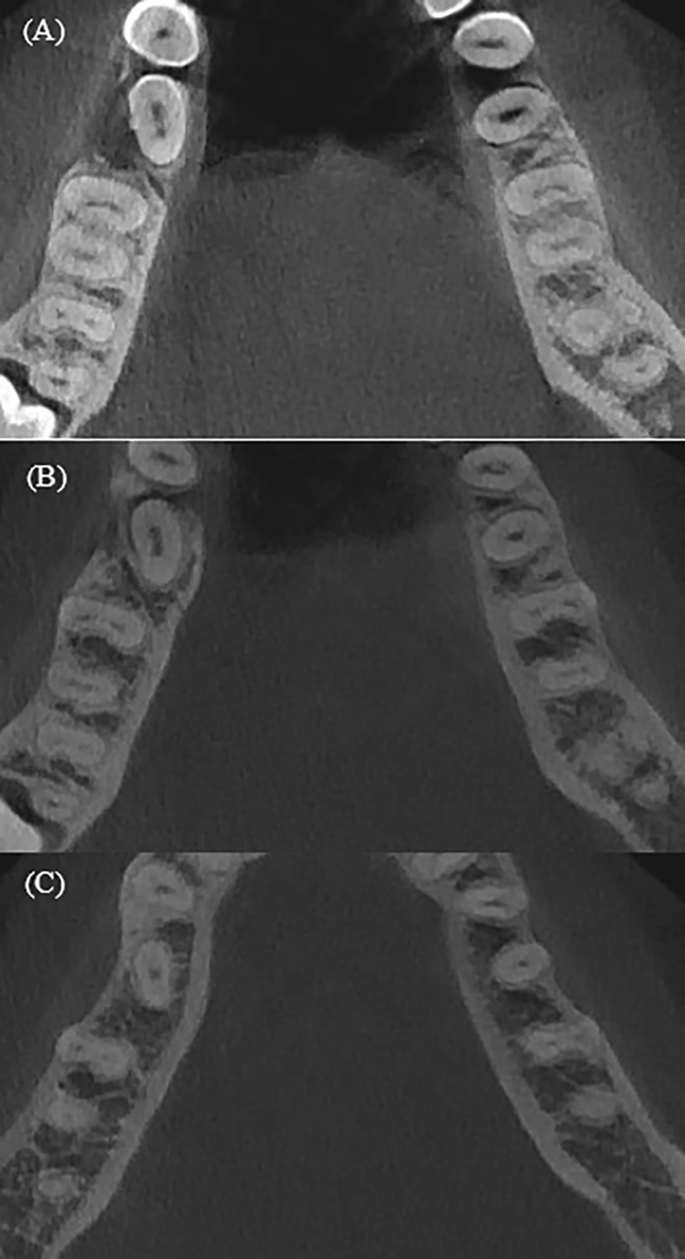

The study of root canal shape at the coronal, middle and apical parts showed that the shape is not constant; it changes depending on the number of canals in the root, the presence or absence of isthmuses. When analysing the maxillary anterior teeth, it was found that the shape of the central and lateral incisors in the upper jaw in 100% is round throughout its entire length (Table 1). The canines of the upper jaw and low jaw are characterized by an oval shape in 100%, which is preserved throughout its entire length (Table 1; Fig. 1). An analysis of the root canal shape of maxillary first and second two-rooted pre-molar showed that in the coronal third round shape was in 37.7% of cases, and oval in 62.3%. In the single-rooted maxillary premolars, in the coronal third, an oval shape, a ribbon-like type 1 and ribbon-like type 5 were revealed. In the middle and apical thirds, the ribbon-like type 1 changes into ribbon-like type 5 (Table 2; Figs. 1 and 2). In the maxillary molars, In MB in the coronal and middle thirds, a ribbon-like type 1 was detected and changed to oval or round in some cases in the apical third (Table 3; Fig. 2).

The mandibular central and lateral incisors are characterized by an oval shape of the root canal, which does not change throughout its entire length in 99% (Table 4; Fig. 3). In the mandibular premolars, the oval shape was found to change in some cases to round or ribbon-like in the apical third (Table 5). For mandibular molars the distal root was found to have an oval or ribbon-like shape of the 1st and 5th types, which changed in some cases in the apical third. For the mesial root in the coronal third ribbon-like shape of the 1st and 2nd types were observed. In the middle third, the number of type 1 ribbon-like decreased by 7 times and they were not detected in the apical part, while the number of ribbon-like of the 5th type in the middle and apical thirds has increased (Table 6; Figs. 4 and 5).

In this study, on the upper jaw oval shape in the apical third was found in canines 100%, premolars 70%, molars 20–30% in the MB, and 14–19% in the DB. The ribbon-like shape of root canal was determined in 14.9% of premolars and in 70.5% of the mesio-buccal root. On the lower jaw, incisors in 99.2%, canines in 100%, premolars in 29.4%, molars in 94.8% have an oval shape in the apical third of the root canal. The ribbon-like shape of root canal was determined in incisors 0.8%, in premolars 6.6%, and in molars: in the distal root 8.8% and in the mesial 95.8%. The data were presented in Table 7.